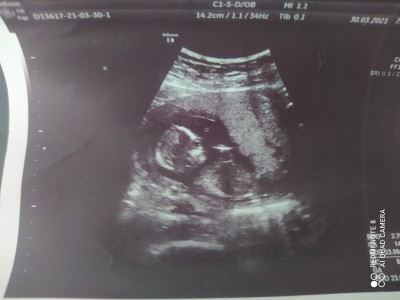

Merhaba arkadaşlar ilk gebeliğim ve cinsiyeti için çok heyecanlıyım göstermiyor daha tahmininiz varmı acaba bir hafta önce çekildi bu ulturasyon fotoğrafı en son

Gebelik haftası 15+5